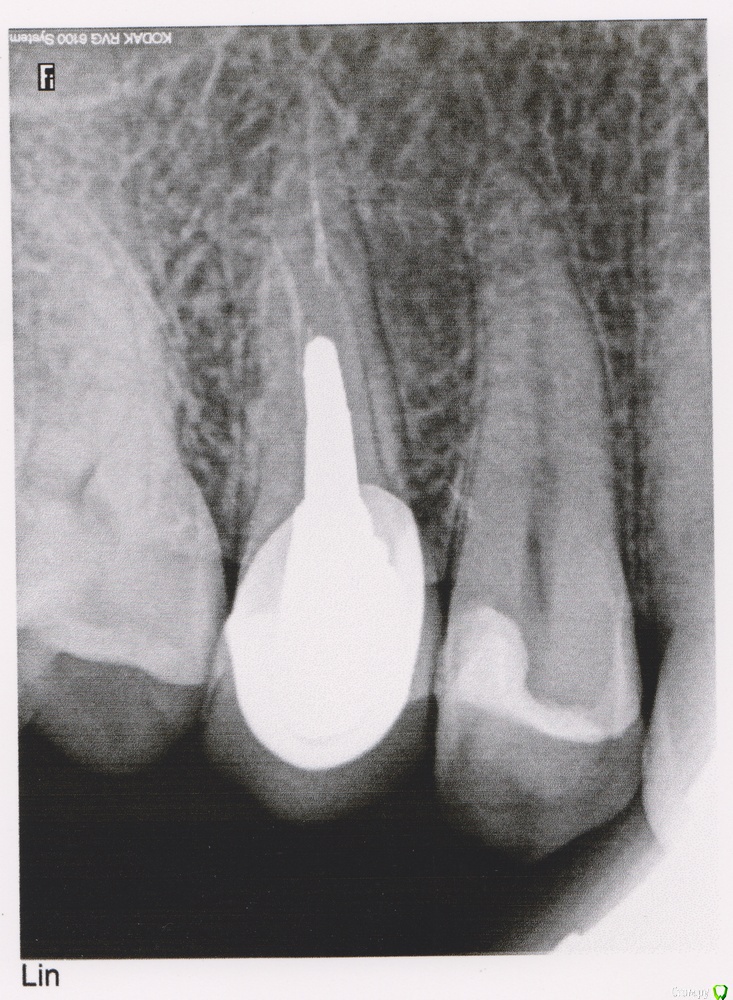

Brim Опубликовано 9 июля, 2015 Поделиться Опубликовано 9 июля, 2015 (изменено) Здравствуйте. Есть у меня многострадальный зуб, на который когда-то сначала поставили пломбу, потом он раскололся, 5 лет назад поставили коронку. Недели 3 назад в районе этого зуба появилось ноющее ощущение. Это не боль, но обращает на себя внимание. При надавливании не болит, не шатается. Вообще никак не болит. При жевании наоборот тянущее ощущение проходит. Пошел к стоматологу - сделали КТ. Сказали, что киста, да аж между зубов - как бы 2ой не зацепила и надо срочно зуб удалять - резекция корня в данном случае невозможна. Но удалять-то это круто, решил перепроверить. К сожалению в других клиниках города только рентген. Был удивлен, когда врач на рентгене не увидел ничего. Сказал была бы сильная боль - отправил бы на КТ, а так - ничего нет. Если есть 2 противоположных мнения, надо проверить еще раз. Пошел к 3 врачу, снова рентген. Снова ничего. Причем настолько, что мол и КТ делать никакого смысла нет, все равно ничего не покажет. А ноет десна, т.е. есть там какая-то щелочка, куда может попадать еда и вызывать воспаление. При этом как только неприятное ощущение появилось - купил какой-то ополаскиватель и вообще все прошло. Но вот он закончился и ощущение появилось снова. Может ли быть такое, что киста не видна на рентгене, но видна на КТ?Получить снимок КТ, к сожалению, возможности нет. Изменено 9 июля, 2015 пользователем Brim Ссылка на комментарий